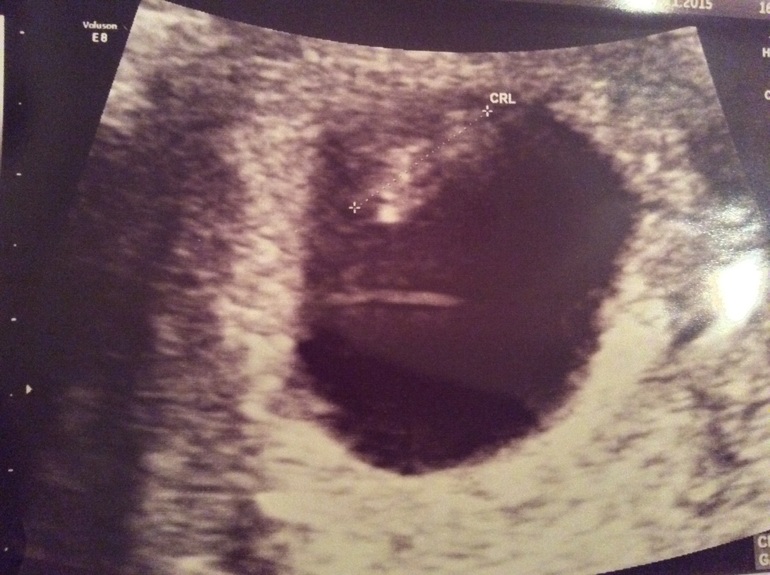

Мы уставились на экран. Я сначала увидела немаленькую матку, растянутую двумя детьми. Через несколько секунд из темноты показалось это!

Был момент, когда неплохо было видно головку и тельце. Увидела трепыхание сердца. На несколько секунд включили сердцебиение. Сделали замер. Почти 13мм. Врач сказал, что похоже на 7 недель и 4 дня. Хорошо развивается! Всё замечательно. Весь осмотр занял минуты 2. Алекс распорядился, чтобы делали максимально быстро и особо не разглядывали. На таком сроке не хотим малыша беспокоить щекоткой от ультразвука.